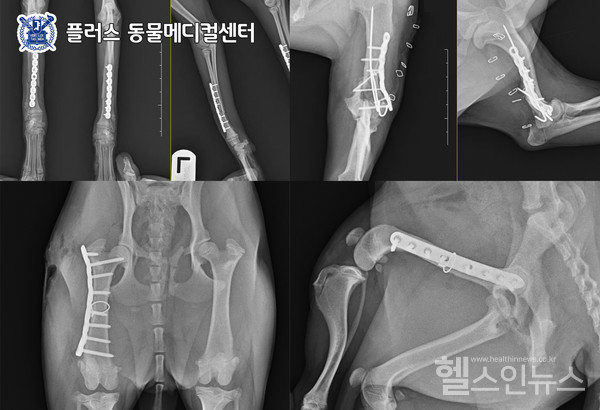

골절수술사진.제공:플러스동물메디컬센터

기본적으로 골절 수술은 뼈의 굴곡에 맞는 플레이트로 부러진 뼈의 배열을 잡아주고 스크류로 고정해주는 방식을 기본으로 진행하지만 케이스에 따라 수내핀(intramedullary pin), 외고정술(IMEX ESF)을 선택하거나 병행될 수 있다. 플레이트, 스크류 방식은 가장 보편적이며 강력한 고정력과 안정성이 장점이지만 발가락 부위처럼 플레이트를 장착하기 힘들 정도의 작은 뼈나 작은 강아지 혹은 골절면이 여러 개이며 구부리거나 회전하는 힘에 저항해줘야 하는 케이스에게는 염증이 생기기 쉽고 골 유합이 불안정할 수 있다. 그럴 때 뼈 안 쪽으로 핀을 심는 수내핀 방식으로 수술법을 결정하거나 복합적인 방식으로 진행하기도 한다.

또한 뼈가 가늘고 다른 종에 비해 골의 회복이 더딘 포메라니안 케이스 등에서는 좀 더 강력하고 오랜 기간 지속할 수 있는 외고정술을 복합적으로 선택하기도 한다. 외고정술은 피부나 근육의 절개를 하지 않고 수술이 가능하며 고정력이 단단하여 단독으로 시행할 경우 출혈과 통증이 적고 회복기간이 단축된다는 장점도 있다. 골절은 흔히 어깨나 발목 탈구도 함께 발생될 수 있어 골절 부위 외의 전신 검진을 통해 추가적인 사고 부위가 없는지 꼼꼼하게 진단을 시행해야 한다. 탈구가 병행되었을 경우에는 골절 수술 외 인대치환술, 인대고정술, 관절고정술을 함께 진행해야 할 수도 있다.